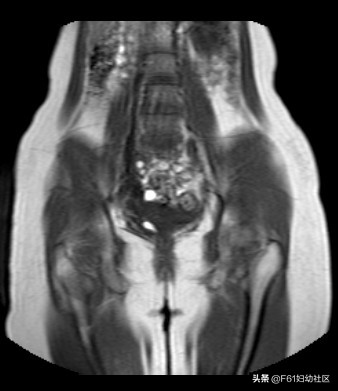

此病人为22岁青年女性,因月经期延长3月就诊,经前一周少量血性分泌物三次至月经来潮。超声提示此患者盆腔可见两个子宫体部及两个子宫颈,附件未见异常。下图为此患者MRI图。

上图为MRI定位相图,隐约见右侧肾窝未见右肾组织。